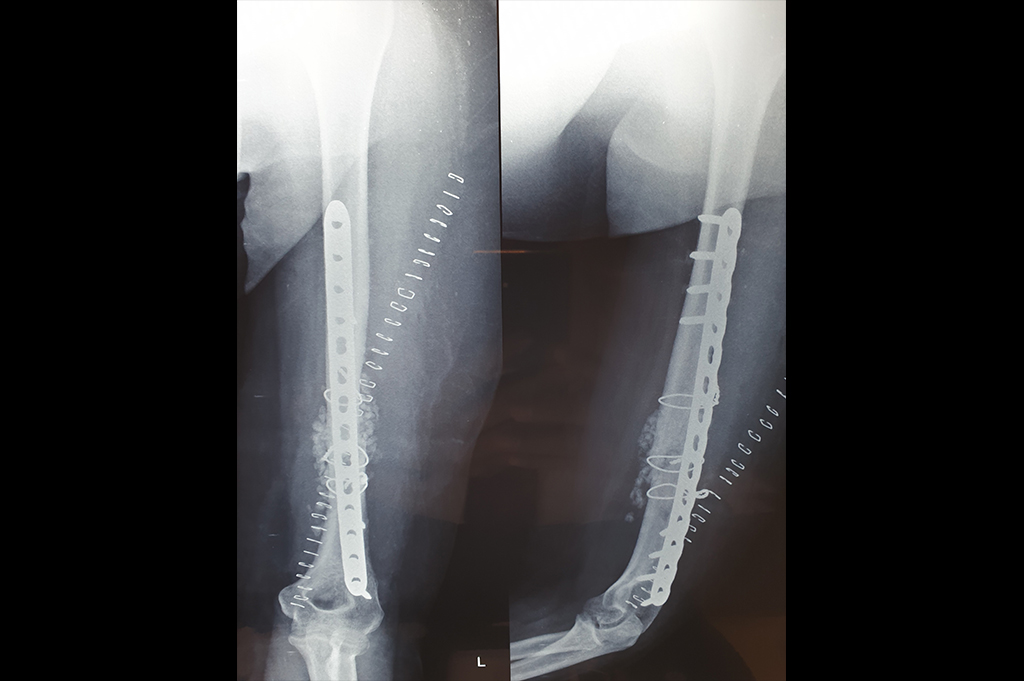

Deformity Correction - Genu Valgum